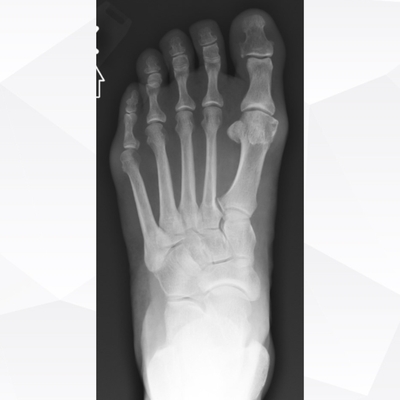

Click on an image below to view more info.